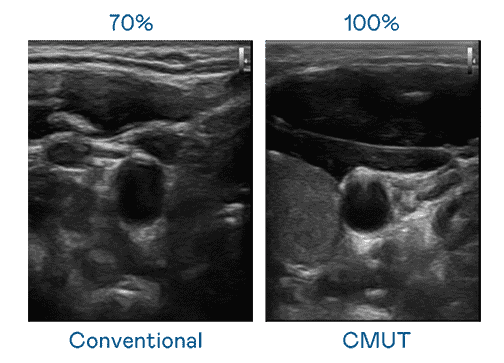

CMUT 技术是一种用电容式微机电元件来产生超音波讯号的技术。。。。与传统 PZT 压电式技术相比,,,CMUT 频宽增加 30%,,,,更宽频的超音波讯号让影像解析度大幅提升,,,是实现高影像品质医疗超音波扫描、、、促进精准医疗发展的关键技术。。

大频宽带来超清晰影像

超音波影像的解析度高低,,,,首先取决于探头能发出的讯号频宽。。918.COM CMUT 可提供高清晰的超音波讯号,,提供高频宽、、、高灵敏度、、、、影像纹理细节更高的超音波影像,,协助医护人员缩短影像判读时间及利用精准的医疗影像进行诊断。。。。